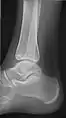

• Ankle - AP/Mortice and Lateral

• Calcaneum - Axial and Lateral